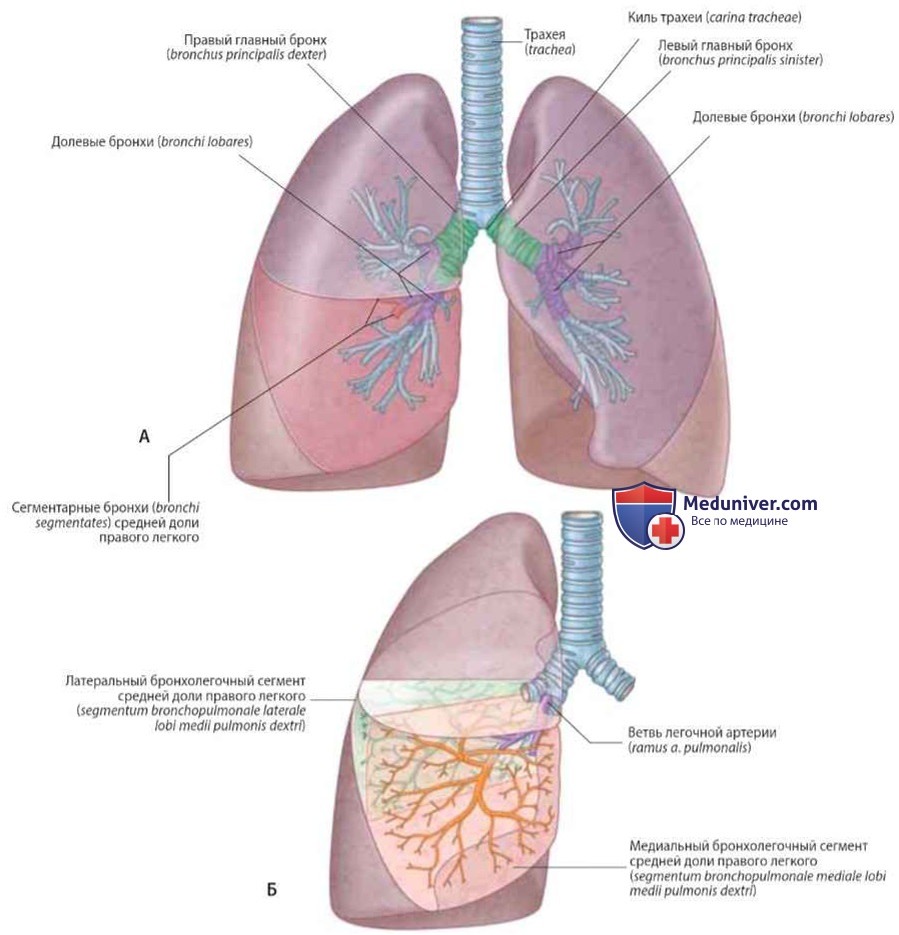

Роль легких в метаболических процессах